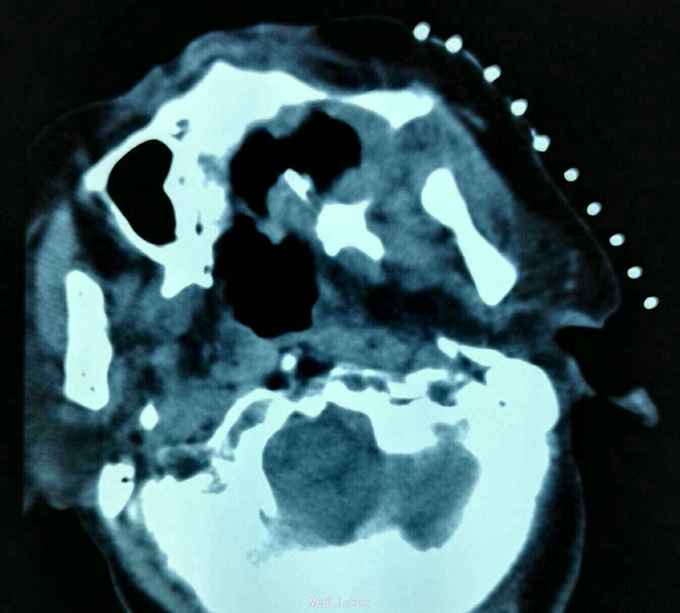

诊断:左上牙龈癌术后复发 治疗:2015.10.21CT引导下行碘125粒子植入术,图为术前定位

肿瘤的治疗应该多元化,该患者属于牙龈癌术后复发,患者不接受放化疗,遂予以碘125粒子植入术,手术成功,嘱患者术后45天返院复诊。